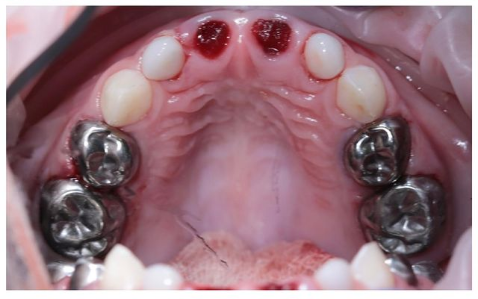

Бутина Елена Александровна: портфолио (8)